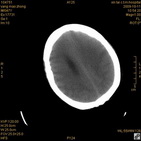

病人杨XX,男,青云街道办事处路踏泉村,住院号51666,CT号:104770。病人因“高血压脑出血”在新泰市人民医院住院治疗5天,治疗效果不佳转入我院,复查CT示左基底节血肿,病人昏迷状态,给予血肿清除术,术后2天复查CT,血肿完全清除,病人恢复好,治疗效果满意。附病人术前术后CT片资料如下。

术后46小时复查CT

术后46小时复查1 术后46小时复查2 术后46小时复查3 术后46小时复查4